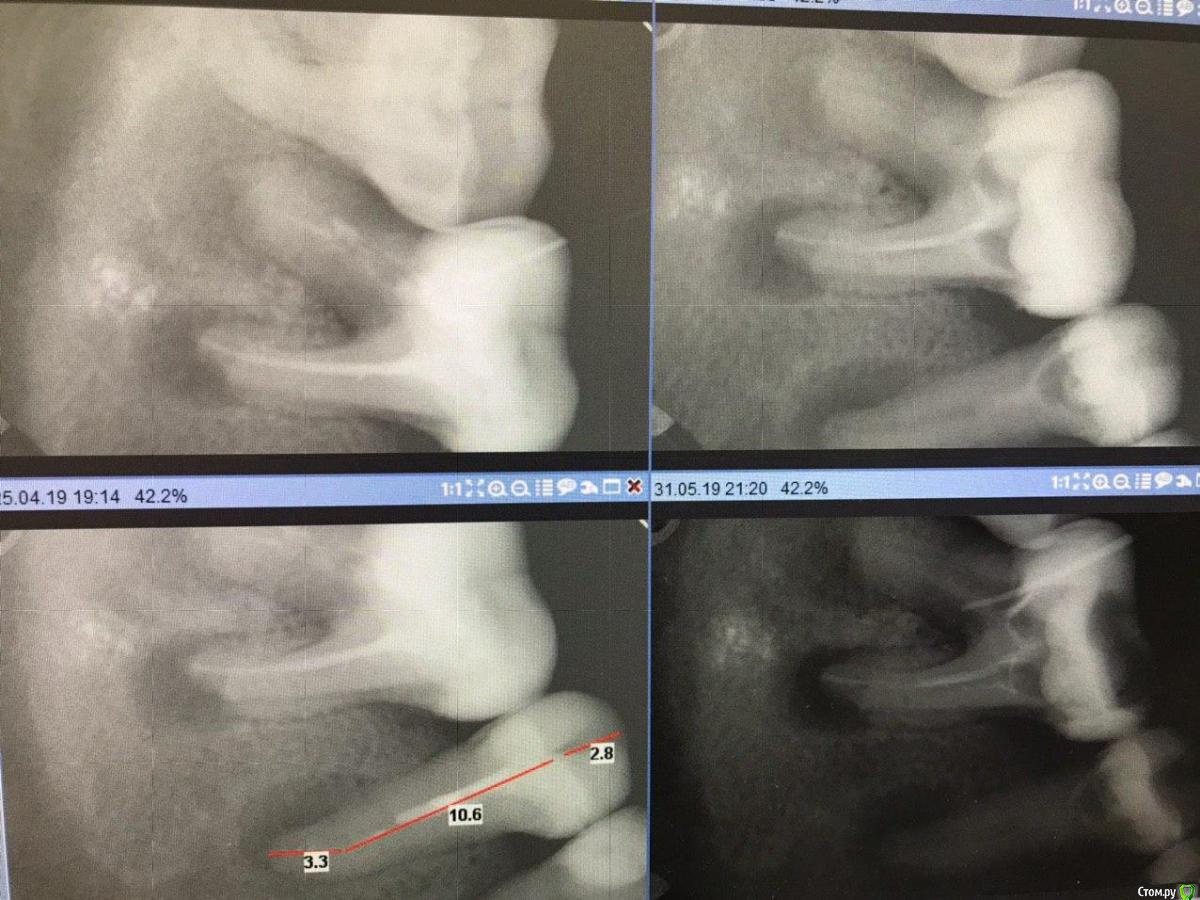

1586Doc Опубликовано 8 февраля, 2020 Поделиться Опубликовано 8 февраля, 2020 5 месяцев назад обратилась пациентка с симптоматикой периодонтита. Оценили, попробовали. Пломбировка вертикалка. 5 месяцев и контроль, боли нет, подвижности тоже. 2 Ссылка на комментарий

1586Doc Опубликовано 9 февраля, 2020 Автор Поделиться Опубликовано 9 февраля, 2020 Сорри с датой ошибка, 9 месяцев ранее Ссылка на комментарий

1586Doc Опубликовано 10 февраля, 2020 Автор Поделиться Опубликовано 10 февраля, 2020 (изменено) А где контроль на сегодня? При таком качестве снимков оценить будет тяжело.первые 2 фото снимки 9 месяц назад, до ревизии Изменено 10 февраля, 2020 пользователем 1586Doc Ссылка на комментарий

Паращук Роман Опубликовано 10 февраля, 2020 Поделиться Опубликовано 10 февраля, 2020 первые 2 фото снимки 9 месяц ранее до ревизии Имхо пока не вижу успеха. (( Ссылка на комментарий

1586Doc Опубликовано 10 февраля, 2020 Автор Поделиться Опубликовано 10 февраля, 2020 (изменено) Имхо пока не вижу успеха. ((ну если еще с 46 я могу понять, 45 явно деструкция в разы меньше. 100% месяца через 3-4 назначу клкт Изменено 10 февраля, 2020 пользователем 1586Doc Ссылка на комментарий

Паращук Роман Опубликовано 10 февраля, 2020 Поделиться Опубликовано 10 февраля, 2020 Ну во-первых,имейте совесть переворачивайте снимки. Шею сломать можно.Во-вторых,у вас позиционеры есть? Только в одинаковых проекциях можно судить,плюс минус,о прогрессе. Ссылка на комментарий

dima3M Опубликовано 15 февраля, 2020 Поделиться Опубликовано 15 февраля, 2020 (изменено) Да, позиционер не сильно поможет, кмк.А КЛКТ точно не помешает.Т.к. имел пример расхождения данных по прицельному снимку и клкт.(последнее показало неудачу, хотя по прицельному-была динамика+) Изменено 15 февраля, 2020 пользователем dima3M Ссылка на комментарий